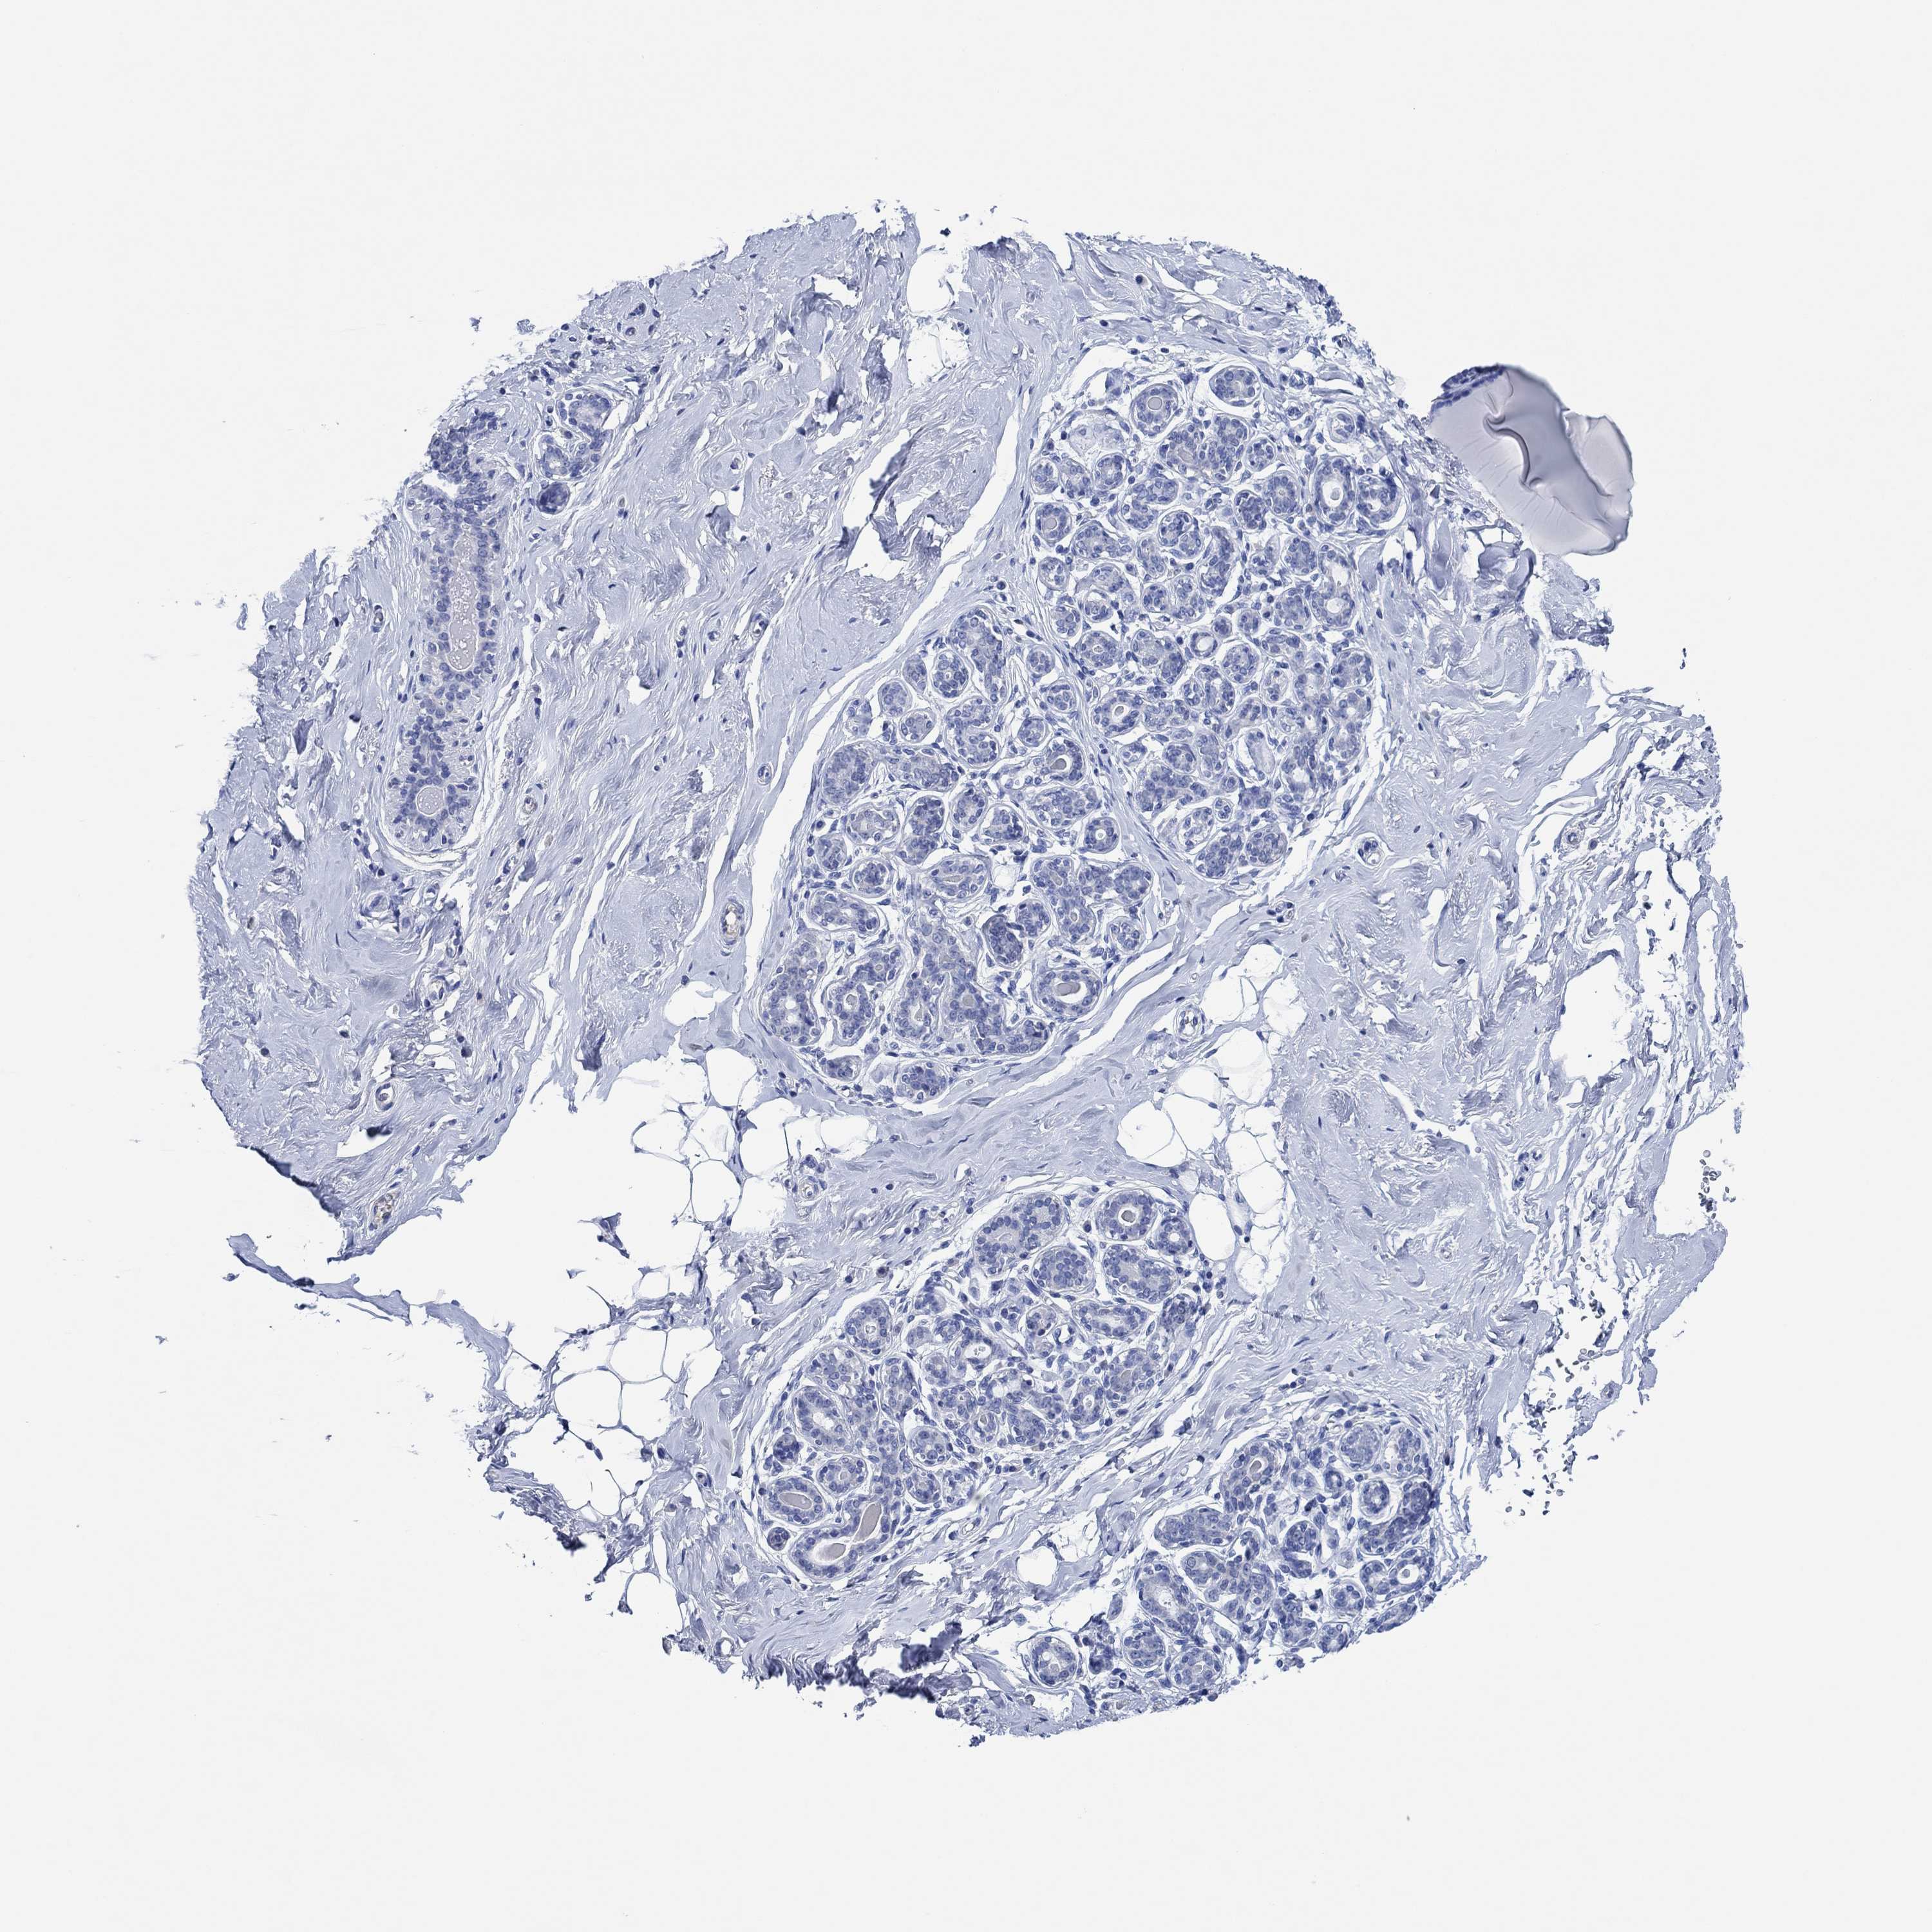

BREAST - Antibody stainingi

Antibody staining in the annotated cell types in the current human tissue is reported as not detected, low, medium, or high, based on conventional immunohistochemistry profiling in selected tissues. This score is based on the combination of the staining intensity and fraction of stained cells.

Each image is clickable and will lead to virtual microscopy that enables deeper exploration of all samples and also displays staining intensity scores, fraction scores and subcellular localization as well as patient and tissue information for each sample.

Antibody HPA031636Antibody HPA076665

Adipocytes Not detectedNot detected

Glandular cells Not detectedNot detected

Myoepithelial cells Not detectedNot detected